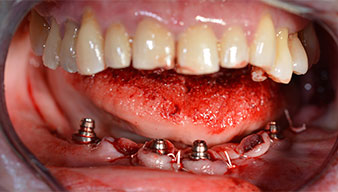

Nach der Entfernung der Unterkiefer-Restbezahnung erfolgte die krestale Schnittführung von Regio 37 bis Regio 47.

Zunächst wurde das Foramen mentale als limitierende anatomische Struktur dargestellt und die krestale Kortikalis mit dem geraden Handstück und einem großen Rosenbohrer geglättet (Abb. 4).

Um die Divergenz der distalen Implantate auszugleichen, werden abgewinkelte Abutments (35 Grad) eingeschraubt, sodass die Austrittsprofile sämtlicher Implantate möglichst senkrecht zur Kauebene stehen. Dies ist Voraussetzung, um die provisorische und später auch die endgültige Versorgung okklusal verschrauben zu können (Abb. 15 und 16).